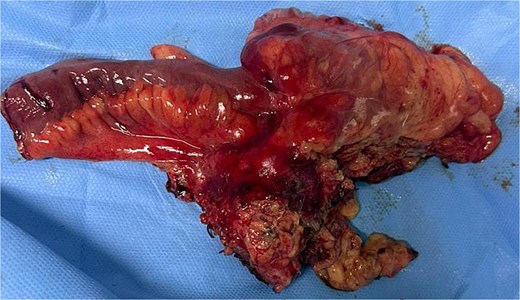

A 29-year-old patient with no significant medical history presented with right iliac fossa pain associated with diarrhea for 4 years, evolving in a context of preserved general condition. Clinical examination revealed tenderness in the right iliac fossa with a good overall state. The biological assessment was normal. The patient underwent a total colonoscopy, which identified non-specific interstitial colitis. An abdominal computed tomography scan was then performed, suggesting an intraperitoneal mass located in the right iliac fossa, containing calcifications and measuring 37 × 49 mm (Fig. 1). The biopsies were non-contributory. The patient was operated on, and surgical exploration revealed the presence of a small intestine tumor invading the base of the cecum. An ileocecal resection was performed (Fig. 2). Histological examination showed a tumor proliferation of fibroblastic nature with variable cellular density, including areas of hypocellular fibrous collagen. There was also an associated lymphocytic inflammatory infiltrate and calcifications. To rule out the diagnosis of gastrointestinal stromal tumors, the main differential diagnosis, immunostaining with anti-CD117 antibody was conducted. The tumor did not express this antigen. The diagnosis of calcifying fibrous tumor was retained.